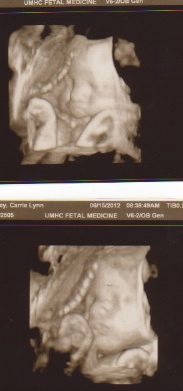

As of today, I've got exactly 3 weeks left (21 days and counting now). I am 34+ weeks pregnant and I've had 31 doctor appointments, 21 ultrasounds, 9 BPP's, 3 echocardiograms, 1 amnio, and 1 MRI.... so far. You can add 6 more ultrasounds and 1 more amnio that I know about in the coming weeks.

Here's a few pics over the last few weeks. The sonographers see me so much that they love

![]() |

| "For the love of all that is holy... STOP looking at me!" ;) |